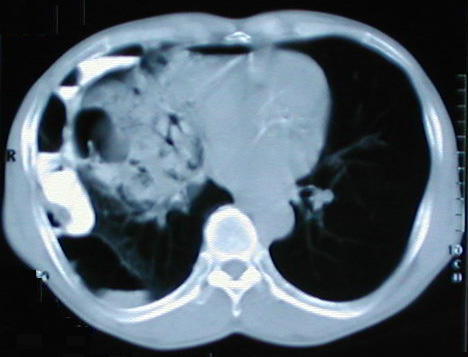

Tomografía de ½ inferior del tórax y abdomen superior con contraste oral, se aprecia desplazamiento del colon hacia la base pulmonar derecha, el campo pulmonar en su periferia y en región subfrénica que comprime y deforma el contorno anterior hepático, también hay contenido de asas delgadas en el tórax.

Corte tomografico del Torax a nivel del tercio inferior del Tórax

Corte tomografico del Torax a nivel inferior de la carina bronquial